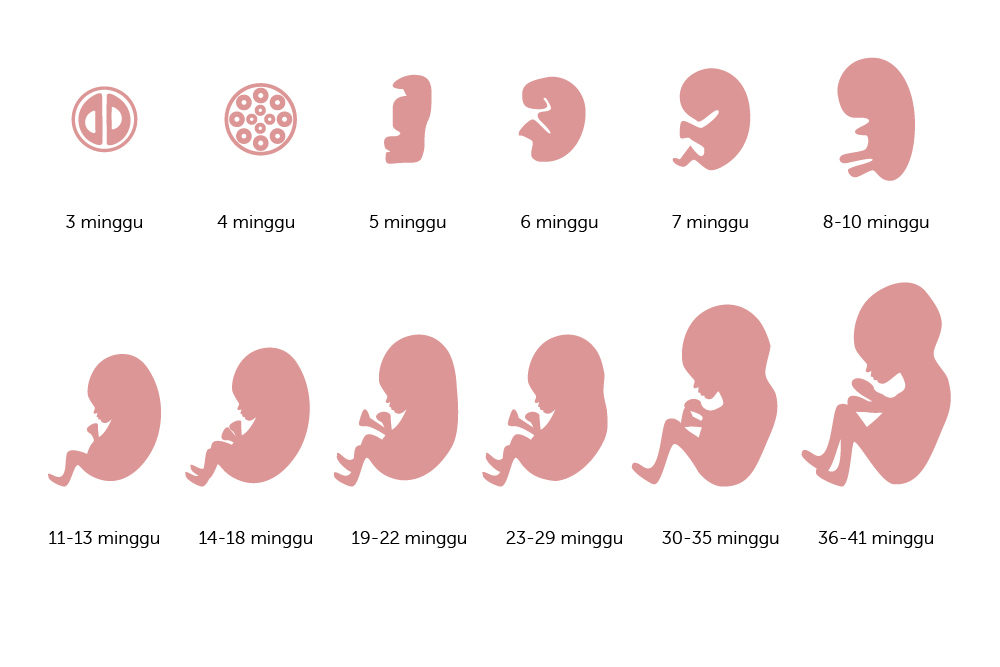

Ini Perkembangan Bayi dalam Kandungan dari Minggu ke Minggu …

Ini Perkembangan Bayi dalam Kandungan dari Minggu ke Minggu …

Perkembangan Dan Posisi Janin Yang Perlu Diperhatikan | Arla Indonesia

Perkembangan Dan Posisi Janin Yang Perlu Diperhatikan | Arla Indonesia

Kehamilan adalah proses berkembangnya em

Kehamilan adalah proses berkembangnya em

Perkembangan Janin di Kehamilan 4 Bulan

Perkembangan Janin di Kehamilan 4 Bulan